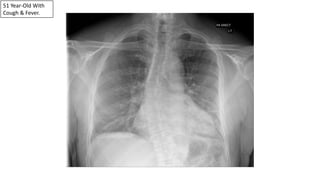

51 Year-Old With

Cough & Fever.

Pneumonias Can Be Subtle On The PA View Alone.

Retrocardiac LLL Pneumonia On The Lateral View